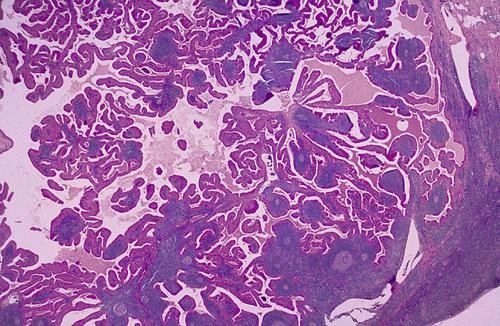

Low-power view showing a papillary cystic tumor with a lymphoid stroma. The epithelium is oncocytic, forming uniform rows of cells surrounding cystic spaces.

Warthin tumor